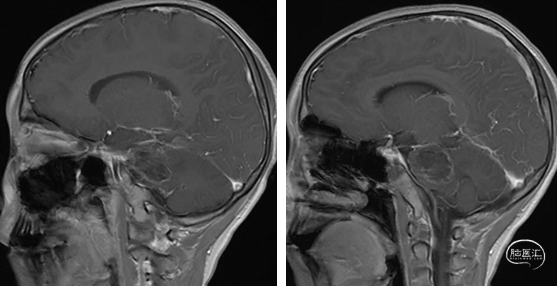

2023年9月13日 MRI T2

2023年9月13日 MRI+C